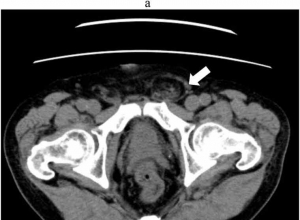

单孔腹腔镜经腹膜外封闭在VAS输精管和睾丸灌注的影响方向和体积-从一个单一的中心的经验Effects of single-port laparoscopic percutaneous extraperitoneal closure on the orientation of the vas deferens and te ...